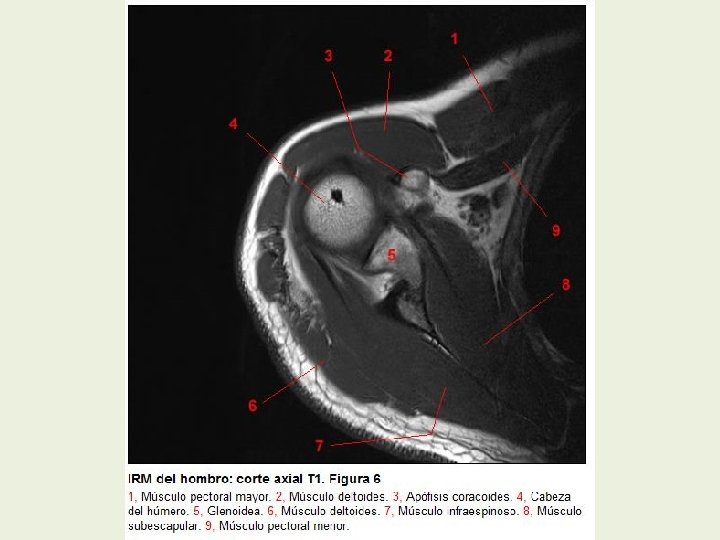

Hombro Cortes axiales RMN